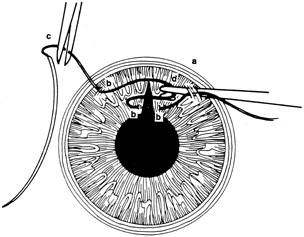

A number of options are available for suturing a corneal laceration. Tissue margins should appose as precisely as possible while suturing. The simplest method is to progressively halve the wound with simple interrupted sutures. Corneal sutures should be approximately 90% to 95% depth through the stroma, 1.5 mm in length, and of equal depth on each side of the wound. Shallow sutures create internal wound gape, whereas sutures of unequal length and depth on each side of the wound result in wound override. Sutures should generally not be passed through 100% thickness because the tract may theoretically act as a conduit allowing microorganisms from the external surface to enter the eye. For shelved lacerations, sutures should be placed equidistant with respect to the internal aspect of the wound and tied with minimal tension to achieve good tissue apposition, avoiding wound slippage with consequent tissue override (Fig. 5). Wounds with edematous or irregular margins generally require longer sutures for closure.

Placement of sutures through the visual axis should be avoided. If it is necessary to pass sutures near the visual axis, they may be placed on each side of, but not directly through, the axis itself. In addition, the bite closest to the visual axis may be made shorter, thus avoiding this area (Fig. 6). A “no-touch” technique also may be used to minimize trauma at the visual axis. With this technique, the eye is secured by grasping the globe with forceps away from the cornea. The suture needle end is then placed perpendicular to the corneal surface, and the needle is rotated through the corneal tissue following the needle's curvature (Fig. 7).8